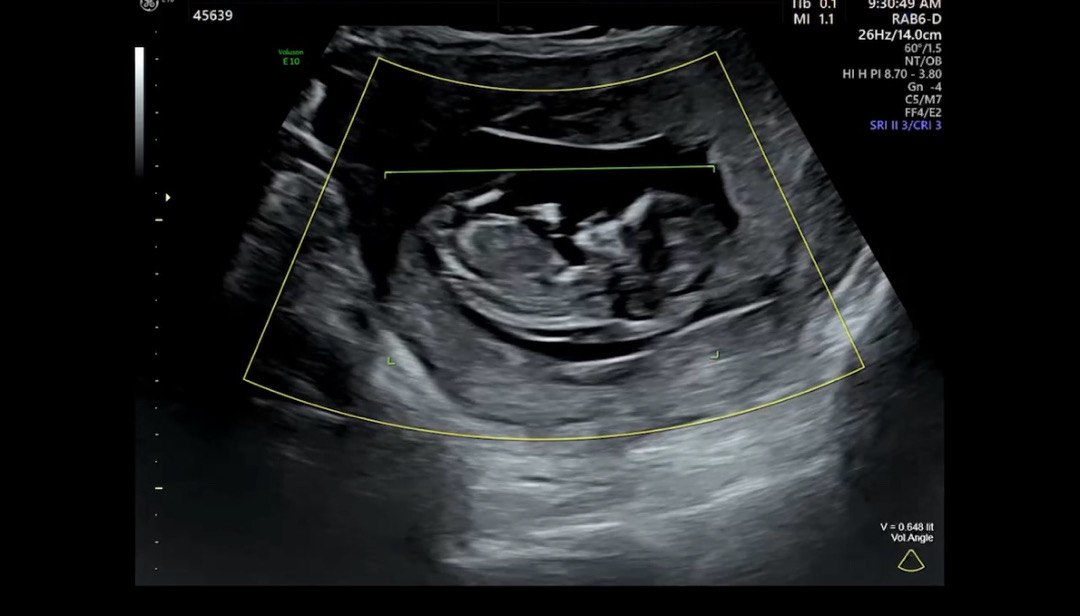

12주 3일이 된 오늘, 1차 기형아검사하러 다녀왔어요! 성별은 1개월 뒤에 알려준다고 하시는데 너무 궁금해서 여쭤봐요!! 각도법 잘 보시는 분들, 어찌 보이시나요?✨